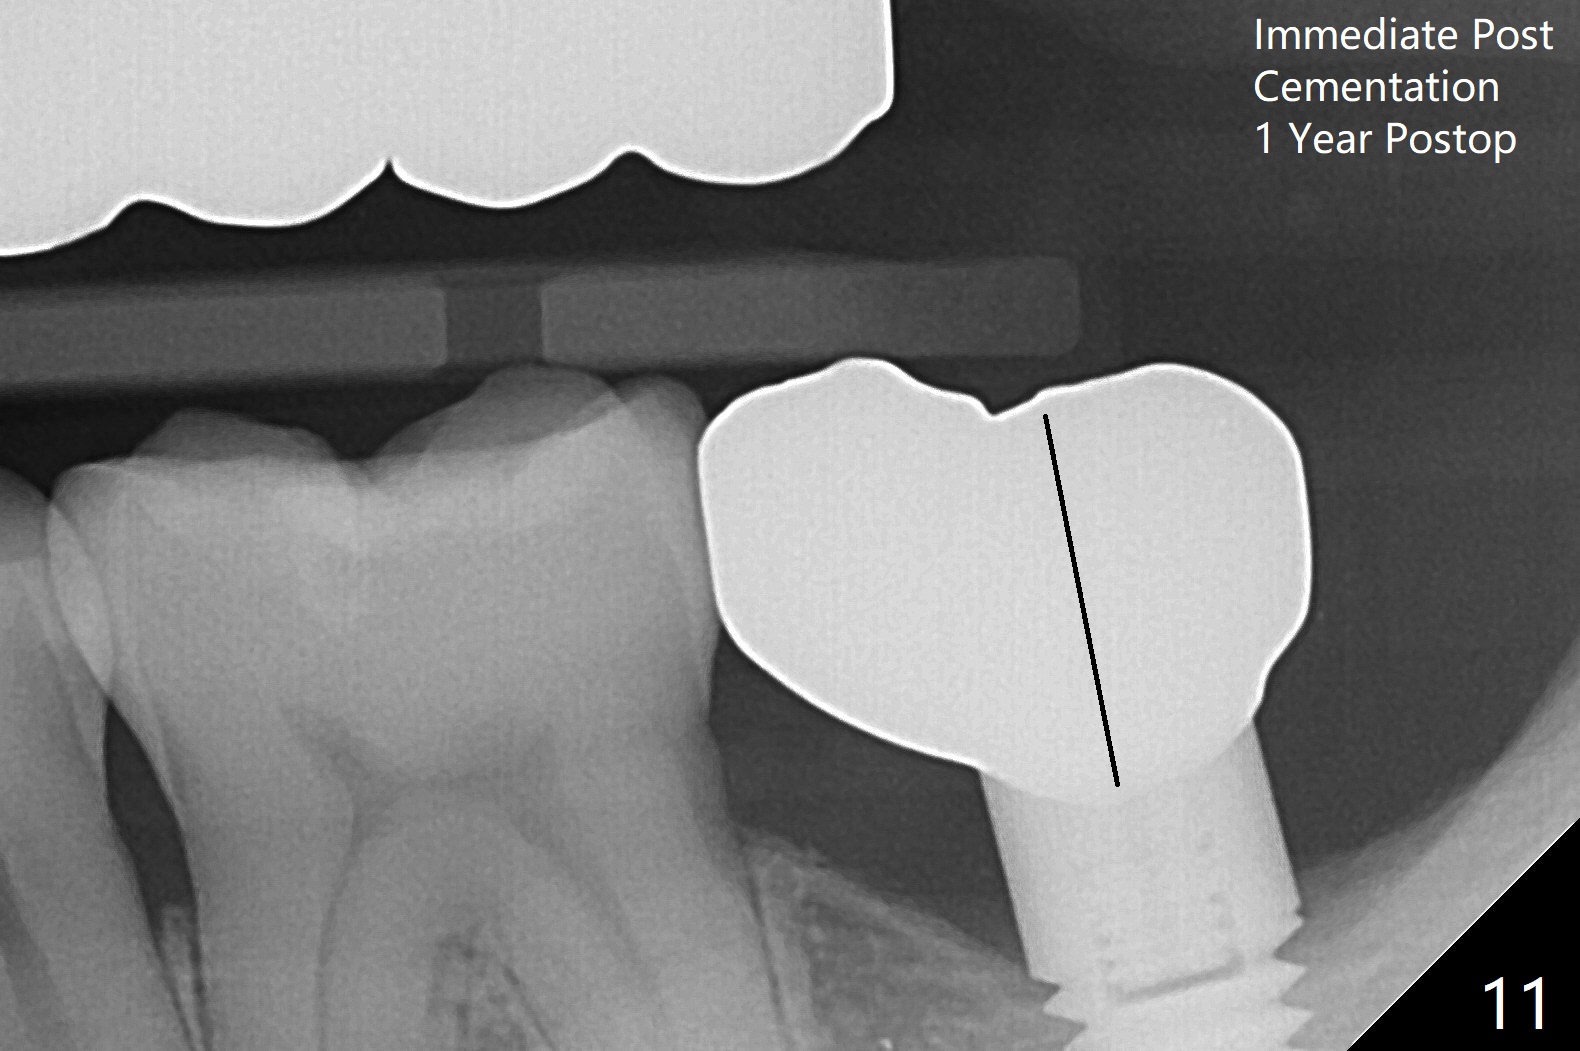

After finishing osteotomy with IS guide and Tatum Tapered tap 5x14 mm for 11 mm (gingival level) free hand, a 5x11 mm Tatum implant is placed at #18 with >15 Ncm (Fig.1). Bone harvested from the site of #18 will be used for #15 sinus lift (Fig.2 * as well as allograft). By the similar fashion, osteotomy at #15 is finished according to IS drill sequence except underdrilling (4.0x7.3 mm drill with 2 O-rings). Following use of DIO Sinus Approach Kit and placement of 2 pieces of PRF membrane and mixture of autogenous and allograft for sinus lift, a 4.5x11 mm IBS dummy implant is placed (Fig.2). With more allograft for sinus lift, a 5x9 mm implant is inserted with >35 Ncm (Fig.3). At #18 the implant 2.5 months postop (Fig.4) seems ok with removal of the cover screw and placement of a healing cuff. The implant at #15 appears osteointegrated with sinus lift 2.5 months postop (Fig.5 *). Half month later, the implant at #18 is tender associated with unipost placement. The healing abutment returns. A pair abutment (5.5x4(4) mm; 25 Ncm) is placed at #15. When the patient returns 7 months postop, BWs are taken to confirm that the abutment at #15 is fully seated, whereas that at #14 is not (Fig.6). A healing abutment is then placed at #14. Osteointegration seems to occur at #18; there is no tenderness when a 4.5x3 mm abutment is placed (Fig.7). Provisional crowns are fabricated at #15 and 18 for progressive loading. When the patient returns 14 months postop, a 5x4(4) mm hex abutment is placed at #14 with apparent gap between the implant and abutment (Fig.8 (PA) open arrow). In fact the gap seems to be absent more coronally as shown by bitewings (Fig.9,10 <). All of the 3 crowns are cemented in situ (Fig.11, 12) although the one at #14 is removed with the abutment for removal of residual cement. When the latter is re-torqued, the abutment remains completely seated (Fig.12). However, the implants at #15 and 18 appear to be placed distally with free-end guides (black lines).